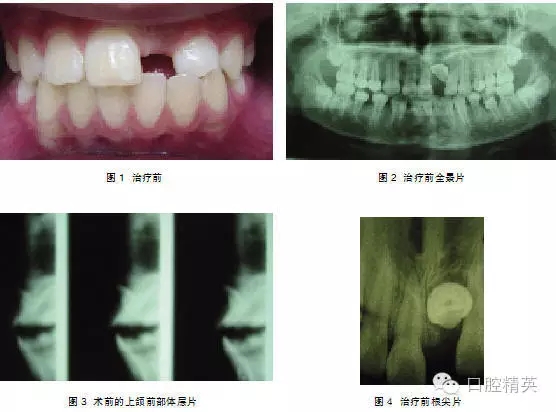

典型病例1: 患者,男,10岁,因左上前门牙未萌出于2009年10月来上海第九人民医院预防、儿童口腔科就诊。检查: |1未萌,1| 全萌,1|2之间间隙为4mm。牙片及全景片示: |1骨内埋伏,1| 2之间有埋伏多生牙,多生牙与 |1的重叠,不能清晰显示多生牙和 |1在颌骨中的具体方位及相关关系(图1-2),采用CBCT扫描后,图像能清晰显示多生牙和 |1的形态、大小、数目、牙根发育情况、在颌骨中具体位置、萌出方向及相互关系(图3-4),经手术证实情况与CBCT图像显示完全一致,手术拔除多生牙, |1作外科开窗术+正畸牵引治疗。